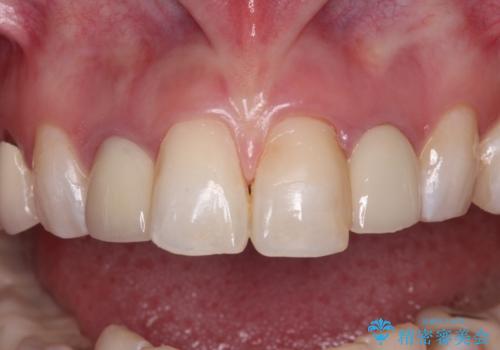

- クラウンから金属の土台が見えてきてしまったとのことで、作り替えを希望して来院された患者様です。

前歯や金属が露出している歯、痛みを感じる歯を中心に、オールセラミッククラウンにて補綴治療することとしました。

以前はセラミッククラウンのフレームとして金属が使用されており、歯肉の経年変化やセラミックのすり減りなどにより、金属が見えるようになってくることがあります。

現在は金属の代わりに強化セラミックを使用したオールセラミッククラウンが主流です。金属色が気になる方はご相談ください。